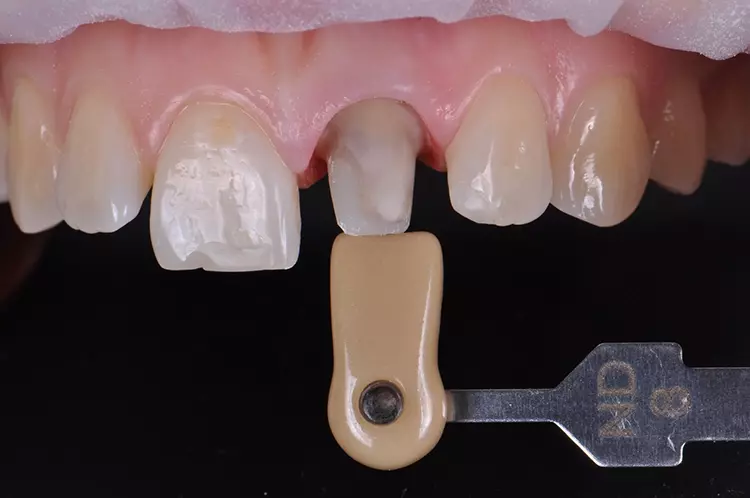

Gleichzeitig wurde mit den initial angefertigten Silikonschlüsseln die anatomische Reduktion des Zahnes 21 visualisiert und die labiale Reduktion in 3 Ebenen bewertet. Die Zielfarbe der Restauration und die Stumpffarbe wurden vor der Abformung für das zahntechnische Labor bestimmt und mit Fotos dokumentiert. Nach Darstellung des Präparationsrandes mittels Retraktionsfaden und Teflonband erfolgte eine klassische Abformung mithilfe eines individuellen Löffels und eines Polyethermaterials (Abb. 11–20).

Die Auswahl des Materials für die definitive Krone wurde in Rücksprache mit dem Zahntechniker getroffen. Sie erfolgte nach der Herstellung der Arbeitsmodelle, der Beurteilung der Platzverhältnisse, der Stumpffarbe und der definierten Zielfarbe. Aufgrund des verfärbten und devitalen Zahnes und zur Vermeidung des „Grauschleiers“ galt es, ein Material mit weniger Transluzenz als Lithiumdisilikat zu verwenden.

Es sollte ein Zirkonoxidmaterial mit hochästhetischen Eigenschaften zum Einsatz kommen. Die Wahl fiel auf IPS e.max ZirCAD Prime, ein Werkstoff der zwei Zirkoniumdioxid-Rohstoffe kombiniert: im Dentinbereich ein 3Y-TZP-Zirkonia mit hoher Festigkeit (1.200 MPa Biegefestigkeit) und im Schneidebereich ein transluzenteres 5Y-TZP-Zirkonia (650 MPa Biegefestigkeit). Der stufenlose Farb- und Transluzenzverlauf in den Materialscheiben ist ein zusätzlicher Vorteil für derartige Restaurationen im sichtbaren Bereich.